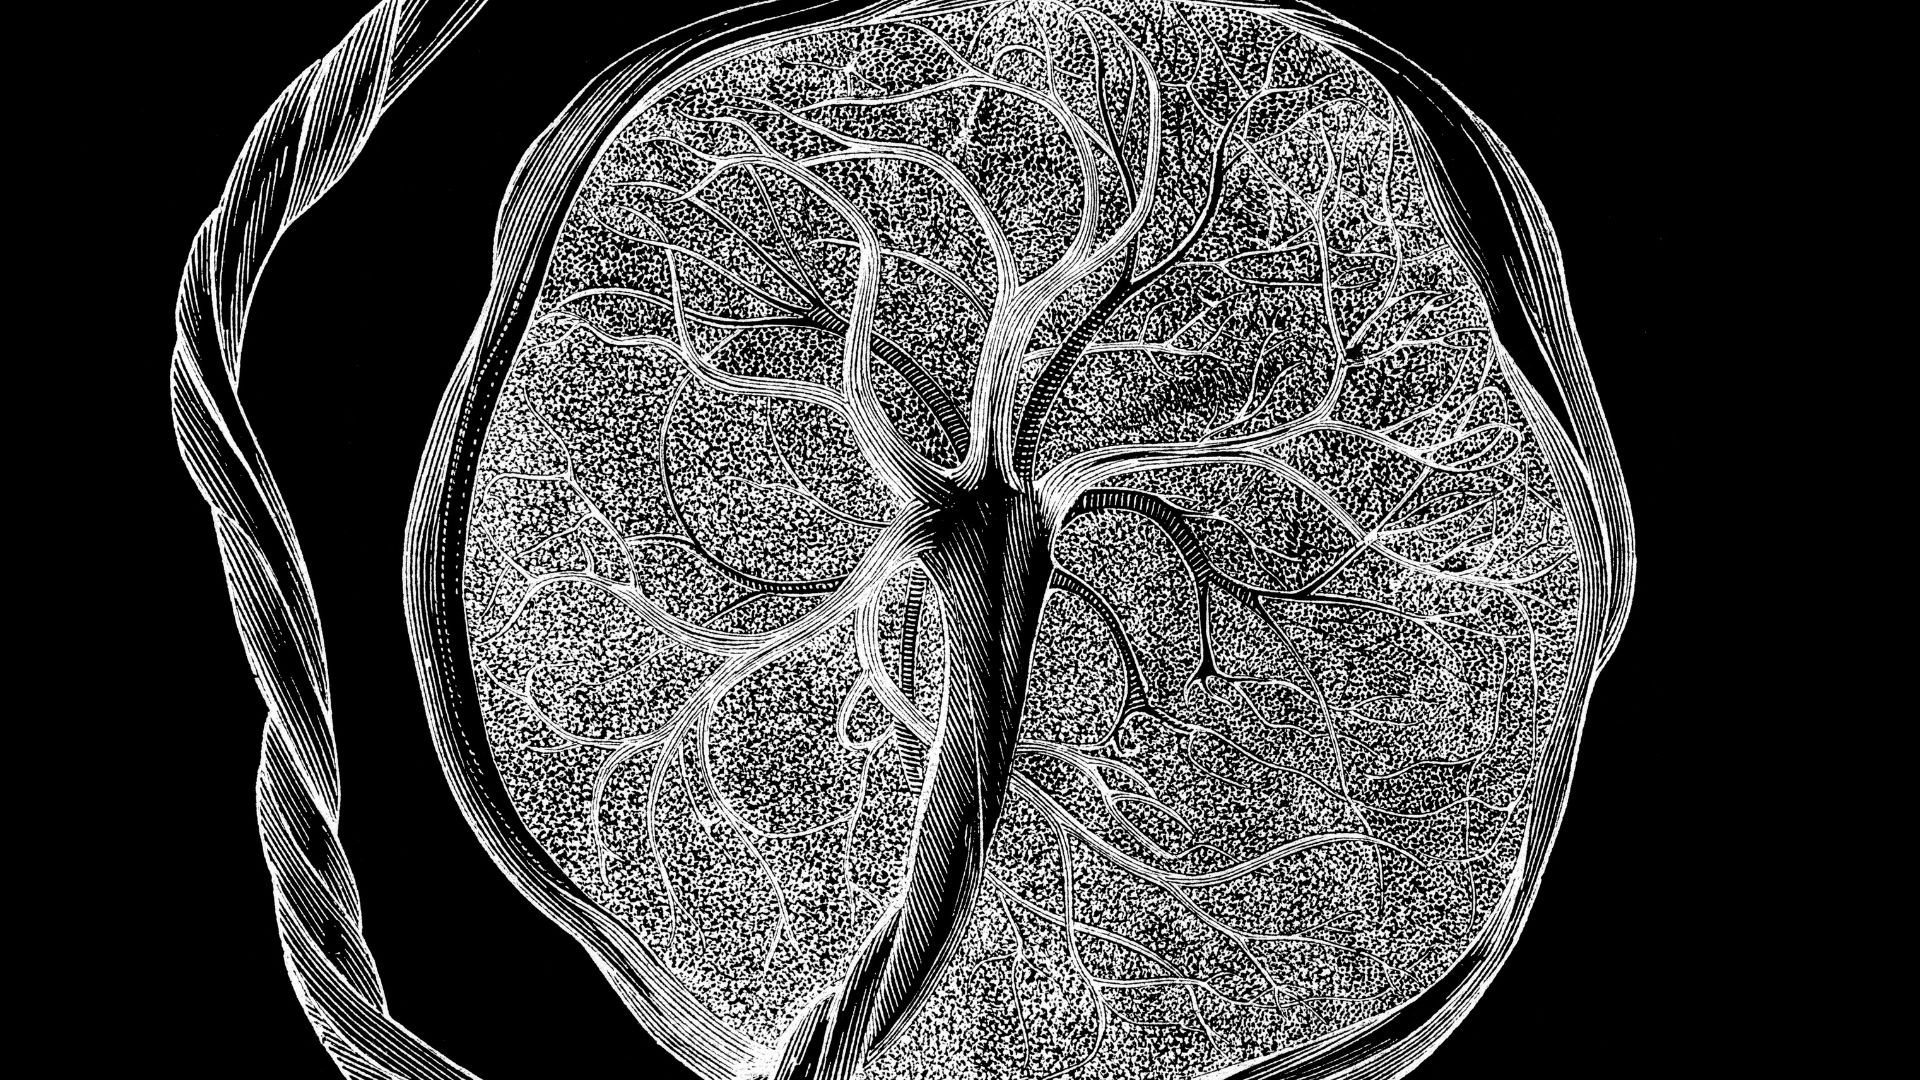

Les scientifiques ont dévoilé un « atlas » détaillé du placenta et de l’utérus, montrant comment ces tissus uniques se développent et évoluent tout au long de la grossesse pour s’adapter au développement du fœtus.

Le laboratoire de Li analyse les tissus de manière très détaillée, à la résolution de cellules individuelles, le développement placentaire étant l’un des principaux axes de recherche de l’équipe. Leur nouvel atlas intègre des instantanés des gènes actifs et des protéines présentes dans les cellules analysées à un stade donné de la grossesse. Il examine également « l’accessibilité de la chromatine », qui reflète la manière dont les molécules d’ADN sont conditionnées dans la cellule et quels gènes peuvent être activés à un moment donné.

Au total, l’équipe a analysé environ 1,2 million de cellules placentaires et utérines, dont 200 000 cellules isolées et 1 million de cellules intégrées à leur emplacement d’origine dans le tissu.